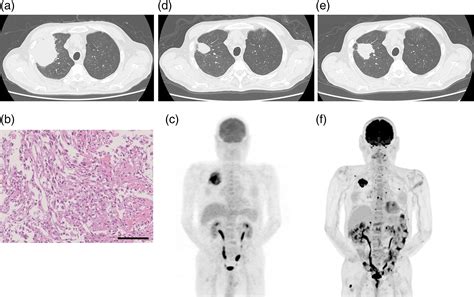

| Imaging (MRI/CT/PET) | Assessing the depth of invasion and checking for potential metastasis. |

Managing this condition effectively requires vigilance and a commitment to follow-up care. Because of the aggressive potential of Spindle Cell Carcinoma, patients are typically placed on a strict surveillance schedule. This usually involves regular physical examinations and imaging studies to detect any signs of recurrence or spread as early as possible. Early detection remains the most powerful tool in improving outcomes. By staying informed about the latest developments in medical oncology and maintaining a proactive approach to symptoms, patients can navigate the challenges associated with this diagnosis more effectively. The focus should always be on quality of life, comprehensive care coordination, and the integration of both clinical and supportive therapies to address the holistic needs of the individual affected by this rare malignancy.